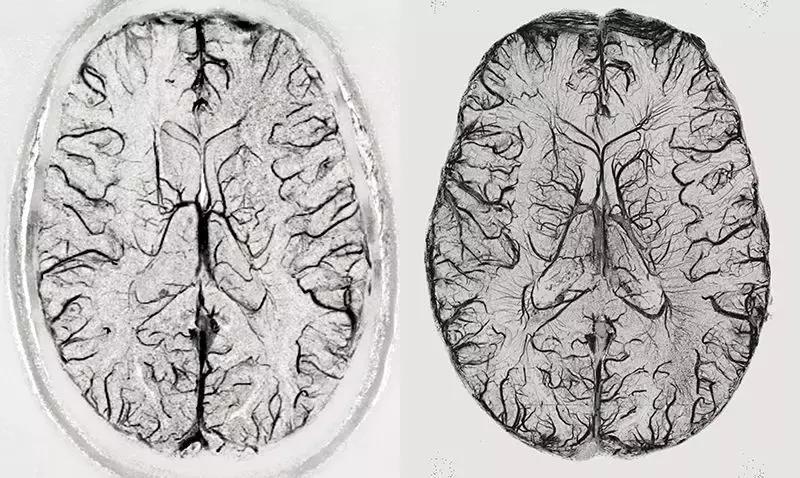

图 | 使用3T(左)和9.4T(右)核磁共振扫描仪的大脑成像对比(来源:Rolf Pohmann/Max-Planck-Institute for Biological Cybernetics)

7T 及更强的核磁共振扫描仪在进行脑成像时,分辨率可达到 0.5 毫米以下,这足以分辨人体大脑皮质区里的功能单位,甚至可以让我们有机会了解活体大脑神经元细胞之间的信息流动情况,为非侵入的精准医学奠定了基础。关于磁共振成像的发现也于 2003 年获得诺贝尔生理学或医学奖。